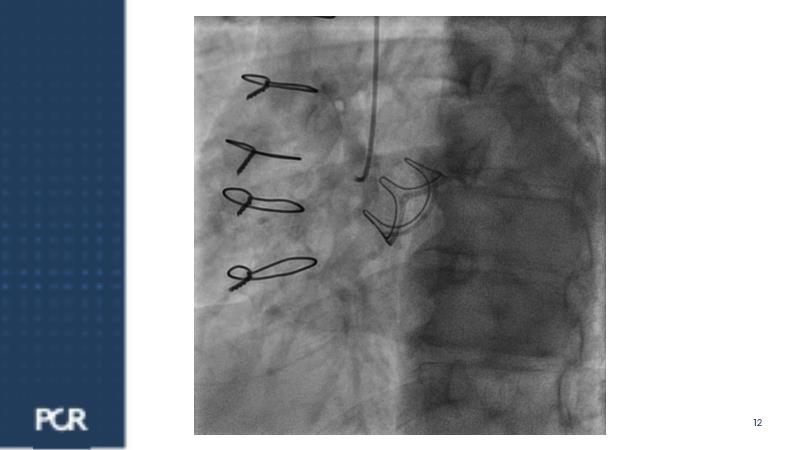

Watch this session focused on a patient with distal left main stenosis to understand that the stepwise provisional side branch (SB) stenting strategy is the standard approach for most left main trifurcation lesions. Discover the importance of optical frequency domain imaging for strategy determination and bifurcation PCI outcome optimization. Learn about the Ultimaster Nagomi™ DES, inheriting features from the Ultimaster Tansei™ stent, tailored for complex bifurcation anatomy with enhanced deliverability and overexpansion capacity.

- To understand the mechanical properties of Ultimaster Nagomi Sirolimus Eluting Coronary Stent System and share the latest clinical results